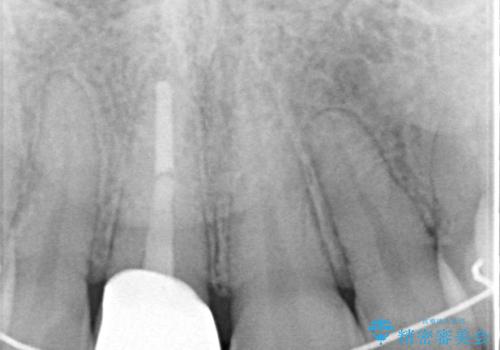

- 以前他院にて保険診療で治療した前歯のやり替え希望の患者様です。

被せものと土台の境目が段差になっています。

審美的にも清掃性の観点からも理想的とは言えない状態です。

ファイバーコアにやり替えて、形を整え直して、

精度の高いシリコーンで型どりしました。

被せものと土台の歯との境目が、歯茎の下に隠れるように調整し、段差もないため、審美性・清掃性のどちらの観点からも理想的な被せものになり、患者様は満足されました。